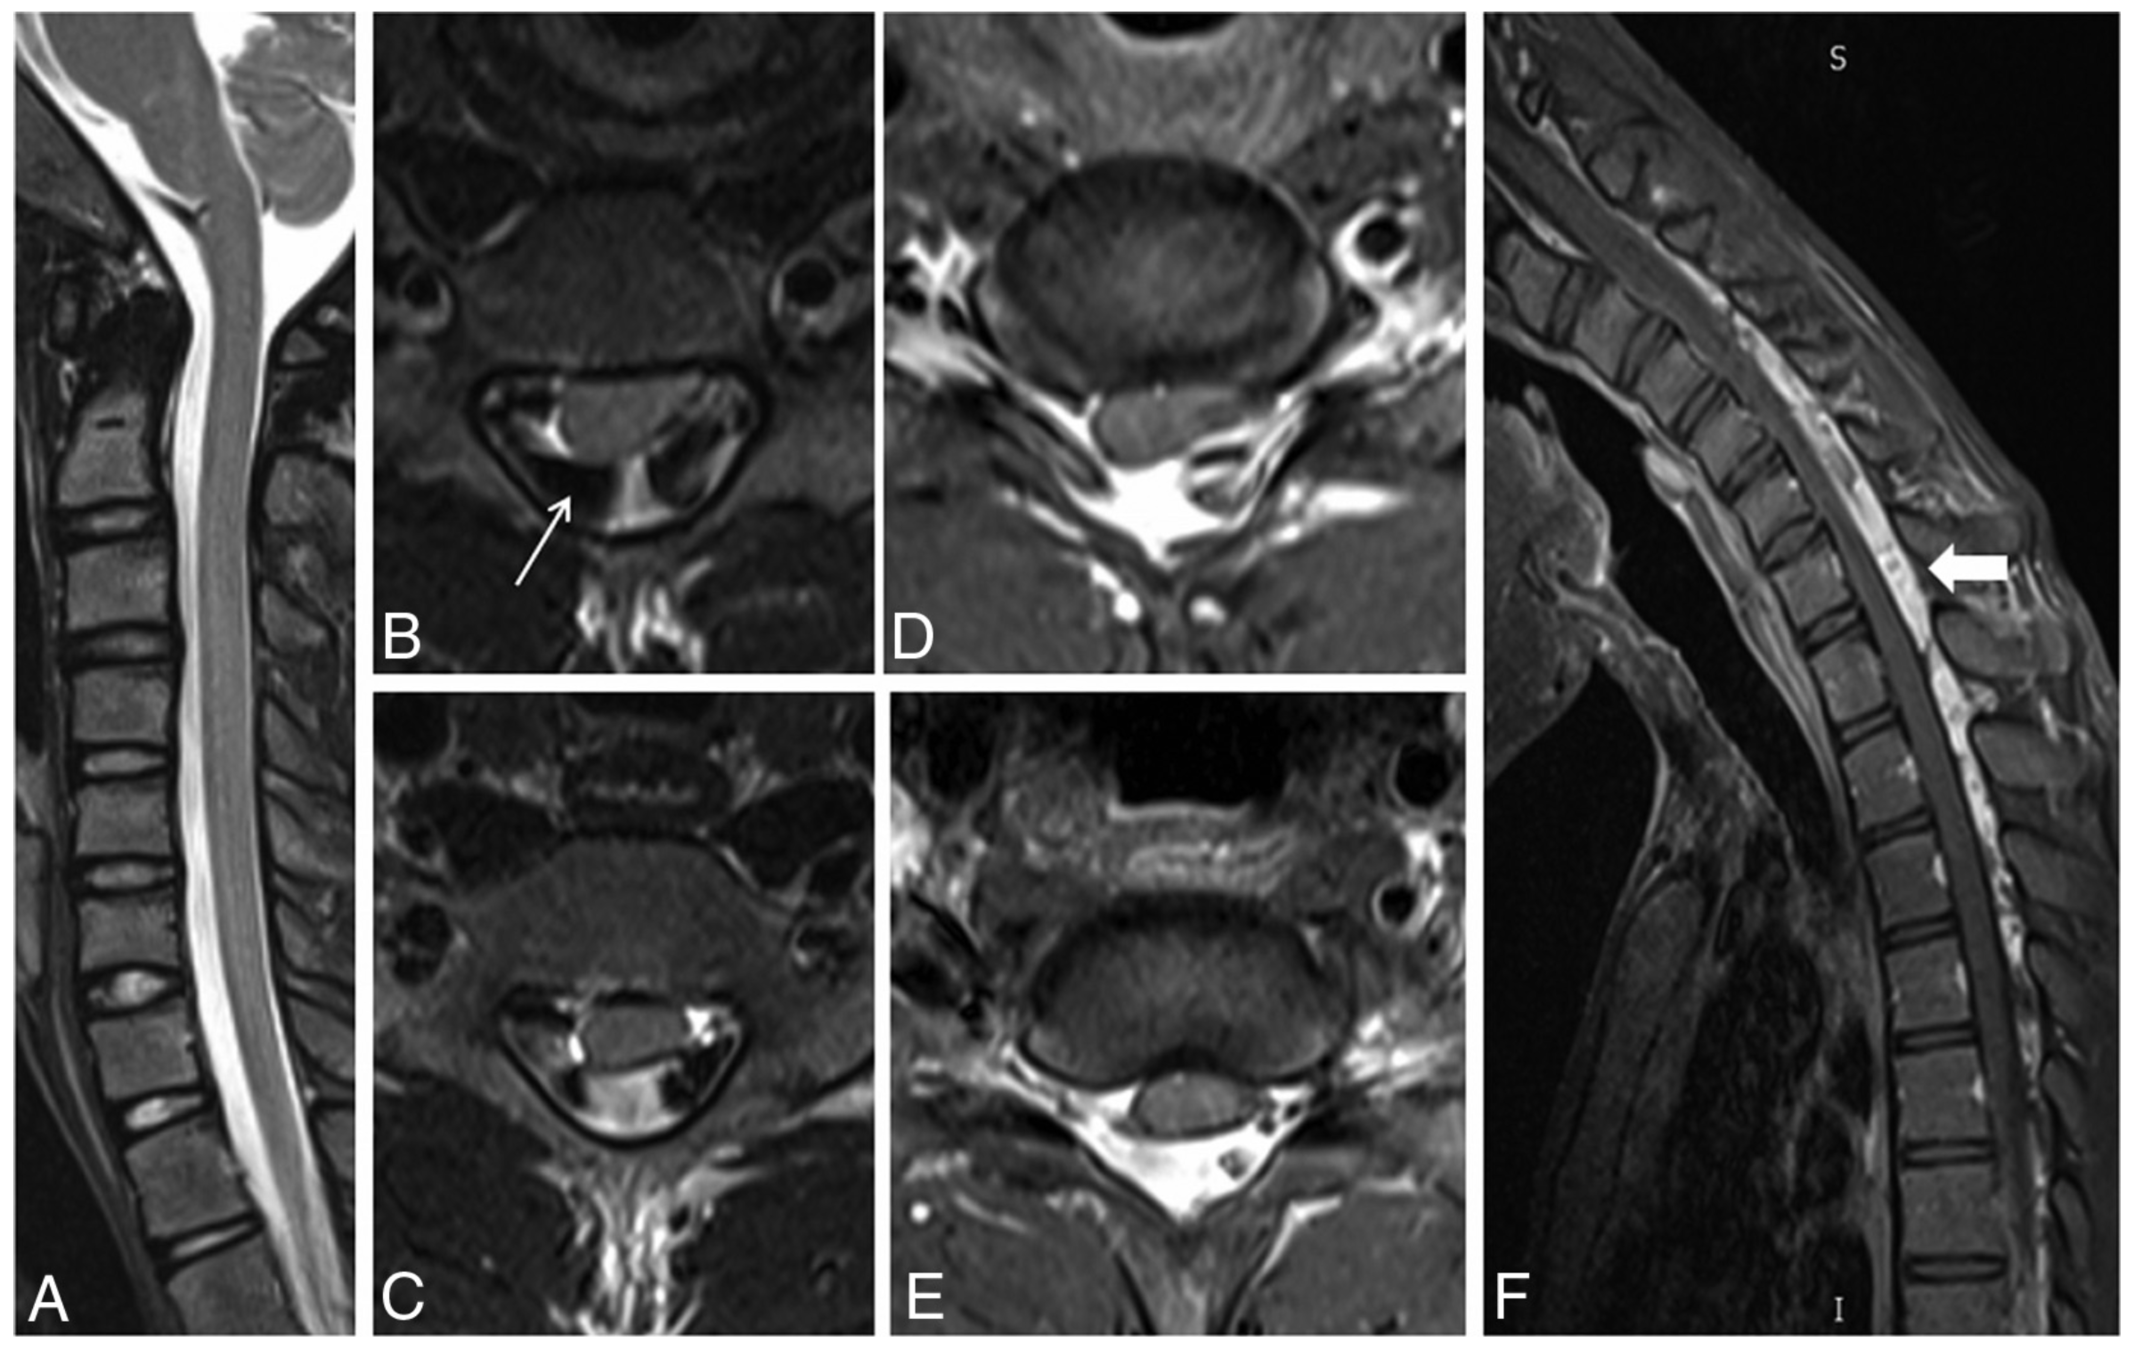

Results

Imaging findings

figs. 4, 5, 6

Imaging important in diagnosis

- Neutral MRI may show atrophy, T2 signal, asymmetric flattening

- Flexion MRI shows classic findings

- Posterior dural detachment -> widened LDS

- Enh of engorged posterior epidural venous plexus

- Compression of cord